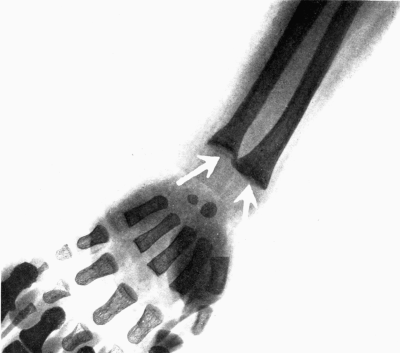

| 6. | Subperiosteal hemorrhage and separation of epiphysis. Roentgenogram | 109 |

| 7. | Complete restitution of epiphysis without deformity. Roentgenogram | 109 |